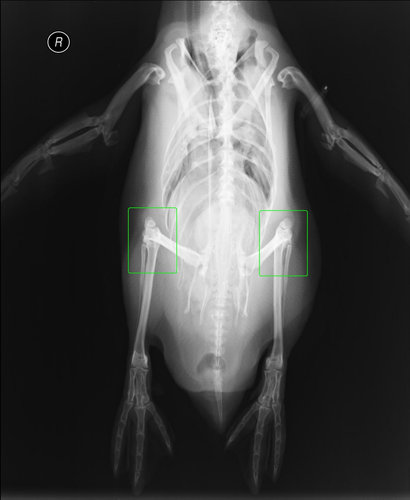

こちらがペンギンのレントゲン写真。

進化の過程で隠れてしまった立派なヒザが、体の中に存在していることがわかります。